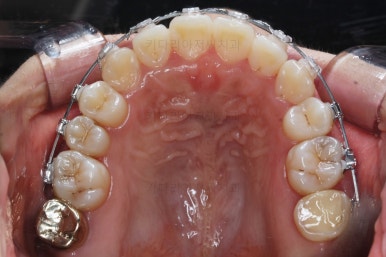

윗니만 추가적으로 발치를 1개 더 했어요.

아랫니는 최대한 추가 발치 없이 후방의 송곳니를 당겨와서 앞니 역할을 하게 했습니다.(총 4개 앞니처럼)

밀고 당기기를 위해서 미니스크류를 셋팅했고요.

교합과 중앙선 및 디테일을 맞춰 나갑니다.